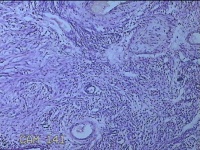

左卵巢囊肿

性别

女

年龄

32岁

临床诊断

左卵巢巧克力囊肿破裂

一般病史

下腹疼痛2天,加重10小时。

标本名称

大体所见

灰白暗红色囊壁样组织5.3x2x1.3cm一堆,表面糜烂,因已切开,囊内容物已流失,囊壁厚0.1cm。

图3